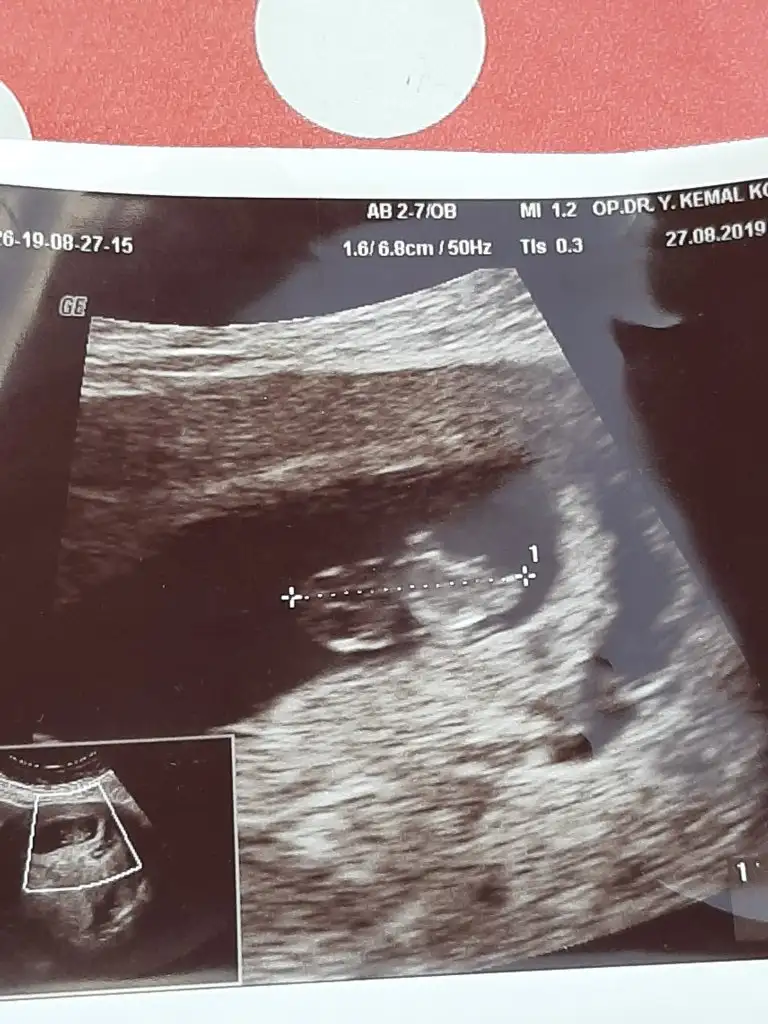

8 buçuk haftalik6 yada 7 haftalık olmalı buna göre erkek ama nub teorisi biraz daha netlik varoda 11 yada 12 hafta usg olmalı

Yok cnm cumartesi tekrar gidicez cok tesekkur ederimmPuslu tatlım erkek gibi ama eminde degilim başka usg varmı tatlım